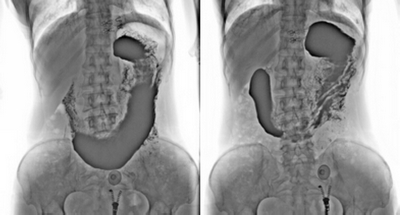

★消除普通數(shù)字胃腸機視野小的缺陷,直接獲得大視野全數(shù)字化圖像 (17x17) 。

★更加方便胃腸、食管、上消化道、全消化道等造影功能!

★通過動態(tài)攝影觀察組織器官的功能運行情況,并輕松進行點片拍攝。

★各種普通及特殊造影,如口服膽囊造影、靜脈膽道造影、T管造影、逆行胰膽管造影(ERCP)、靜脈腎盂造影(IVP)、子宮輸卵管造影、脊髓造影等。